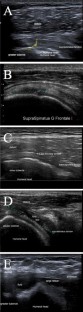

Fig. 1

Fig. 2

Fig. 3

Fig. 4